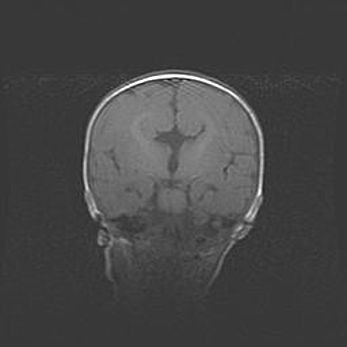

Неполная лизэнцефалия (пахигирия). Открытая гидроцефалия.

Возраст: 17 дней

Вес: 3110 г

Пол: мужской

Окружность головы: 33,5 см

Срок гестации: 35-36 недель

Лизэнцефалия—недоразвитие корковой пластинки и мозговых извилин в результате нарушения миграции нейронов коры. Поверхность мозговых полушарий гладкая. Микроскопически выявляется отсутствие нормальных слоев коры и скопление групп нейронов в подкорковом белом веществе.

Пахигирия—уменьшение числа вторичных извилин. В пораженном полушарии нервные клетки образуют толстый недифференцированный слой с неправильно расположенными нервными волокнами и группами гетеротопных клеток. Нервные клетки незрелые. Белое вещество истончено. При этом нередко аномально развит корково-спинномозговой путь.